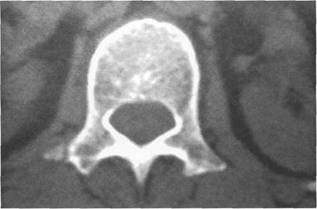

К моменту рождения (рис. 3.1) тело позвонка почти полностью состоит из к 141s183b 86;стной ткани, за исключением лимбусов, которые остаются хрящевыми. Дуга представлена двумя половинами, не слившимися ни с телом позвонка, ни между собой. Суставные отростки сохраняют перифе

MPT. Cw_v.